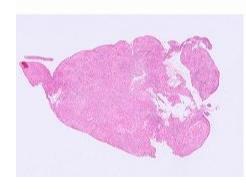

The main types of liver biopsy for histopathological assessment are Tru-cut needle, wedge and laparoscopic biopsies. Wedges are preferred (by pathologists!) – Figs 1 and 2 below explain why.

Fig 1. Wedge biopsies – pros and cons

Fig 3. Canine liver lobule with central vein (CV) in middle and portal tracts (PT) on the periphery – this lobule measures ~1mm diameter. An entire lobule is generally only captured via a wedge biopsy.